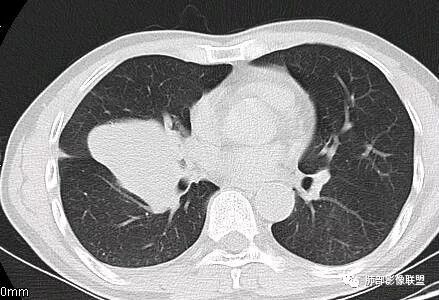

这一个类圆形,边界光滑,明显膨胀生长为主,如果起源中叶支气管,按理中叶支气管不动,固定在中叶支气管上,推移其他结构

但是现在的片显示,其主体在下叶,中叶支气管壁由下朝上有推移

南边:就不符合这个原理

初学者:如果中叶病灶,叶间裂应该下推,也不会上推

而且支气管內密度较高是粘液栓,远端支气管也是通畅,所以支气管内是因为受压所以痰液引流不畅。